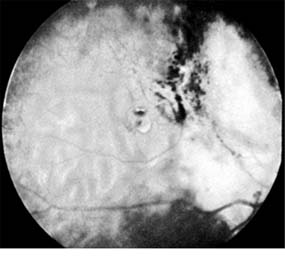

Figure 10-34

Figure 10-34: Retinoblastoma after radiotherapy.

Enucleation is the treatment of choice for large retinoblastomas. Eyes with smaller tumors can be effectively treated with plaque or external beam radiotherapy (Figure 10-34), cryotherapy, or photocoagulation. Chemotherapy is being used to reduce the size of large tumors prior to other types of therapy and occasionally as the sole form of therapy. It is also used to treat tumors that have extended into the brain, orbit, or distally and may be used after enucleation in patients at high risk for such widespread disease.